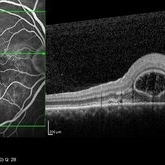

Vogt Koyanagi Harada

Oct 7 2015 by Avris Romario Diparaja Siahaan

A FA and OCT of a 42-year-old woman with Harada Syndrome in both eyes.

Photographer: Yohanes Harry Purwanto, Klinik Mata Nusantara

Imaging device: Heidelberg HRA + OCT

Condition/keywords: optical coherence tomography (OCT), Vogt-Koyanagi-Harada